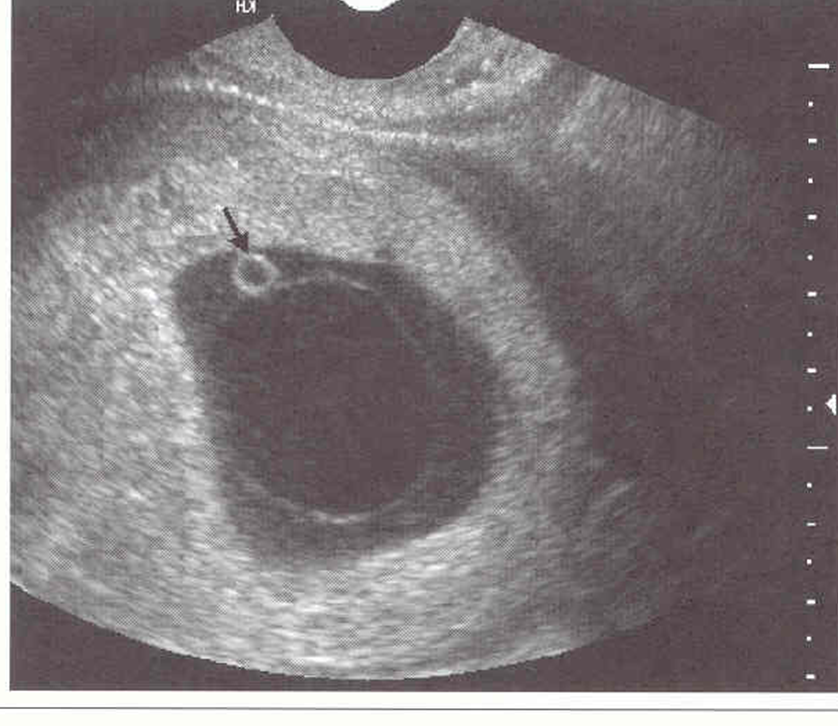

NOT BLACK ARROW

dark ring around gest sac

choronic cavity

darkest circle

amniotic cavity

thin white curved line at top

amniotic membraine

1 – decidua capsularis

2- Chorionic membrane

3 – amniotic cavity

4 – chorionic cavity

5- yolk sac

6 – decidua basalis